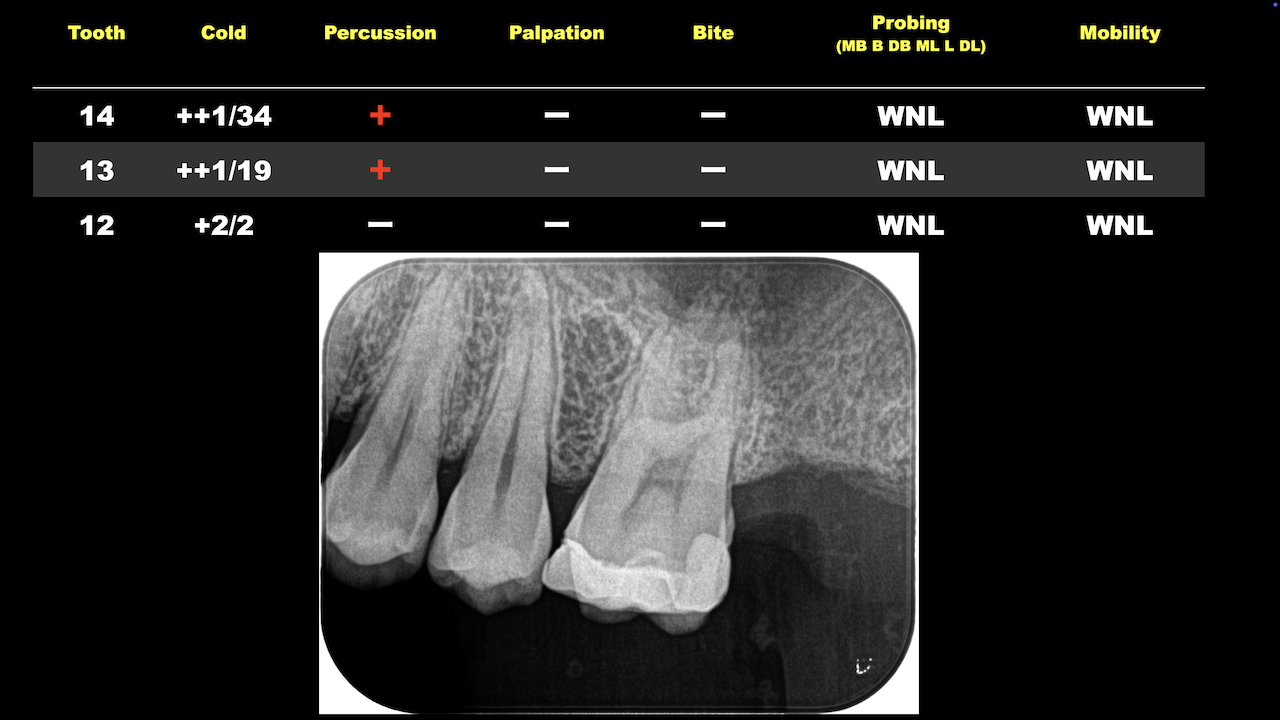

#13,#14ともにSymptomatic irreversible pulpitisで根管治療の適応症である。

#14の方が痛みが強いということだったので、まずはそこから行った。

そして、別日に#13のRCTを行った。

そこで、2yr recallをこれらの歯に行うことになる。

すると、

#13に臨床症状が出てしまっている。

CBCTを撮影すると、

同じ治療をしたにもかかわらず、#13に根尖病変ができている。

これは一体何が理由だろうか?